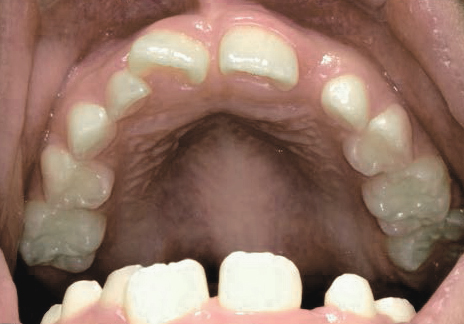

Before

After

上あごの成長が少なく、特に前歯のガタガタが目立っていました。口呼吸のクセや飲み込み方に良くないクセが確認されました。

治療を終えて

マイオブレイスとBB1装置で上あごの成長を助け、鼻呼吸や正しい飲み込み方を身につけることで、きれいな歯並びとしっかり噛めるお口に変わっていきました。

姿勢やお口の機能を正しく整えたので、後戻りしない綺麗な歯並びを維持できています。もちろん非抜歯です。

主訴・治療内容 当院と交流のある歯科医師の先生が、ご自身のお子さまの治療を任せてくださいました。

「難しい歯並びでも永久歯を抜かず、全身の健康と顔立ちも考えて治療してくれる」と信頼していただいて治療開始。

治療期間 3年

費用 462,000円(税込)

リスク・副作用

• 治療の初期段階では、痛みや不快感が生じやすくなりますが、一週間前後で慣れます。

• 歯の動き方には個人差があるため、予想された治療期間より延長する場合があります。